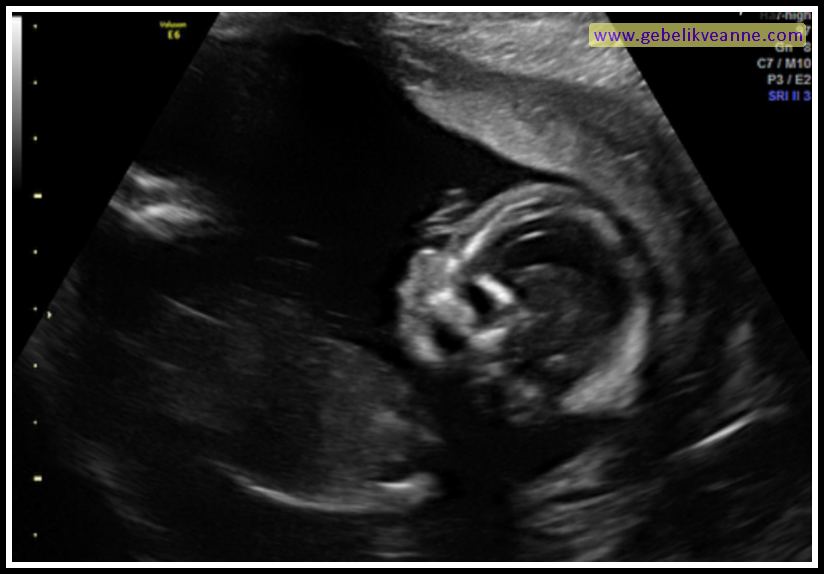

17 haftalık bebek görüntüsü

17 haftalık bebek görüntüsü Bebek hızla büyüyüp gelişirken 17 haftalık gebe de bu değişimlerden bedenen ve ruhen etkileniyor. 17 haftalık gebelik görüntüsü incelendiğinde bebeğin boyunun önceki haftanın neredeyse iki katı olduğu görülür. Bebeğinizin hücre sayısı her gün iki katına çıkıyor >. Haftada rahminiz yukarı ve dışarı doğru hareket etmeye başlar. Rahiminiz göbek deliği seviyesine ulaşmak üzere ve bunu elinizle hissedebilirsiniz. Hamilelikte gelişim süreci hızlı olmaya devam ederken anne adaylarını n en çok merak ettiği konu bebeğin ultrason görüntüsü oluyor. Bu hafta bebeğin kas yapısı ve hareketleri de gelişecektir. Bebeğiniz bu dönemde tam olarak görünümünü almıştır.

Haftasında fetüsün boyu baştan kalçaya yaklaşık 11,6 cm ölçülür ve ortalama ağırlık 100 g’dır. Haftadan itibaren kendi kendine hareketler yapıyor, kol ve bacaklarını oynatıyor. 17 haftalik gebeli̇k (hami̇leli̇k) görüntüsü. Haftada bebeğinizle hemen hemen aynı büyüklüğe ulaşır. Bu hafta bebeğin kas yapısı ve hareketleri de gelişecektir. 17 haftalık bebek ultrason görüntüsü.

Gebelik haftasında bebeğin boyu yaklaşık 13 cm, ağırlığı 150 gram kadardır. 17 haftalık gebelik görüntüsü kapsamında bebek içinizde hızla büyüyor.akciğerleri gelişiyor, soluk alma ve verme refleksleri gelişiyor.17 haftalık bebek refleksleri son derece gelişkindir çünkü dış dünyaya hazırlanması gerekiyor. 17 haftalık gebelik ultrason görüntüsü ile birlikte bebeklerin gelişimi daha 17 haftalık gebelik 3 aylık 29 günlük yani 119 günlük gebesiniz. 17 haftalık gebelik görüntüsü incelendiğinde bebeğin boyunun önceki haftanın neredeyse iki katı olduğu görülür. Haftadan itibaren kendi kendine hareketler yapıyor, kol ve bacaklarını oynatıyor.

Tüm hatları belirgin bir hale geldiği için çok rahat bir şekilde cinsiyet hakkında data verilir. Plasenta ve göbek bağı artık net olarak görülebiliyor. İşte 17 haftalık gebelik ultrason görüntüsü.